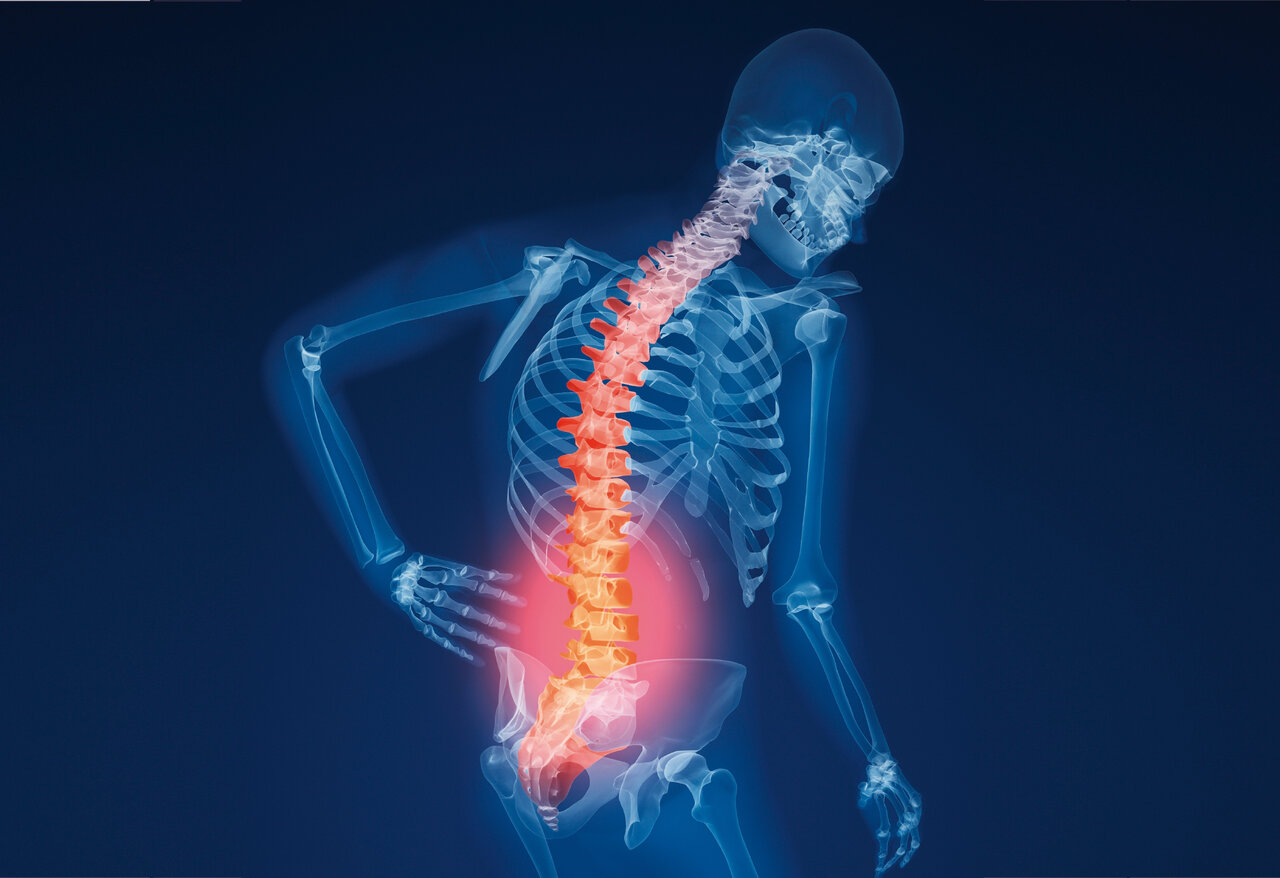

پوکی استخوان (Osteoporosis) یکی از بیماریهای شایعی است که بسیاری از افراد در سنین بالا به آن مبتلا میشوند. پوکی استخوان درواقع کاهش تودهی استخوانی بدن محسوب میشود. استخوانها در بدن ساختار خاصی دارند و از دو لایه تشکیل شدهاند. درواقع استخوان یک لایهی داخلی و یک لایهی خارجی دارد.

لایهی داخلی دارای ساختاری متراکم است که شکلی شبیه لانهی زنبور دارد، ضمن اینکه بافت آن بسیار محکم است. زمانی که اتصالات تیغههای استخوانی کم شوند یا ساختار میکروسکوپی خاص آنها به هم بریزد، در چنین شرایطی، استخوانها میتوانند دچار شکستگی شوند.

در این حالت استخوانها نمیتوانند بار و وزنی را که از بدن به آنها وارد میشود، تحمل کنند. به عبارت روشنتر، وقتی تودهی استخوانی کاهش پیدا میکند، کمیت استخوان دچار تغییر میشود و وقتی تراکم استخوان کاهش مییابد، کیفیت آن تغییر پیدا میکند، درواقع تیغههای بین استخوانی پوک و اتصالات آنها در اثر ابتلا به پوکی استخوان، سست خواهند شد.